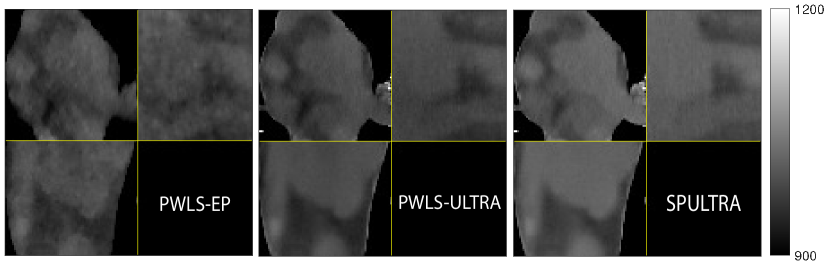

Fig. 4 shows the reconstructed images and the corresponding error images for PWLS-EP, PWLS-ULTRA, and SPULTRA, at and . Compared to the PWLS-EP result, both PWLS-ULTRA and SPULTRA achieved significant improvements in image quality in terms of sharper reconstructions of anatomical structures such as bones and soft tissues, and suppressing the noise. However, the PWLS-ULTRA method introduces bias in the reconstructions, which leads to larger reconstruction errors compared to the proposed SPULTRA method. In Fig. 4, we marked three 3D ROIs in the axial plane, i.e., ROI 1, ROI 2, and ROI 3. Fig. 5 shows the zoom-in images of a 3D plot of ROI 1, and those of ROI 2 and ROI 3 are shown in the supplement. We also plot the evolution of RMSE through the axial slices of the three 3D ROIs in Fig. 6. The figures demonstrate that SPULTRA clearly outperforms the competing PWLS-EP and PWLS-ULTRA schemes.

The above advantages of SPULTRA can be seen more clearly when observing the image profiles. Fig. 7 plots the image profiles for the three methods together with that of the ground-truth image. Fig. 4 shows the horizontal green solid line and the vertical red dashed line, whose intensities are plotted in Fig. 7. It is obvious that the profiles for SPULTRA are closest to the ground-truth among the three compared methods. The gap between the profiles of the PWLS-based methods and the ground-truth shows the bias caused by the compared PWLS methods.